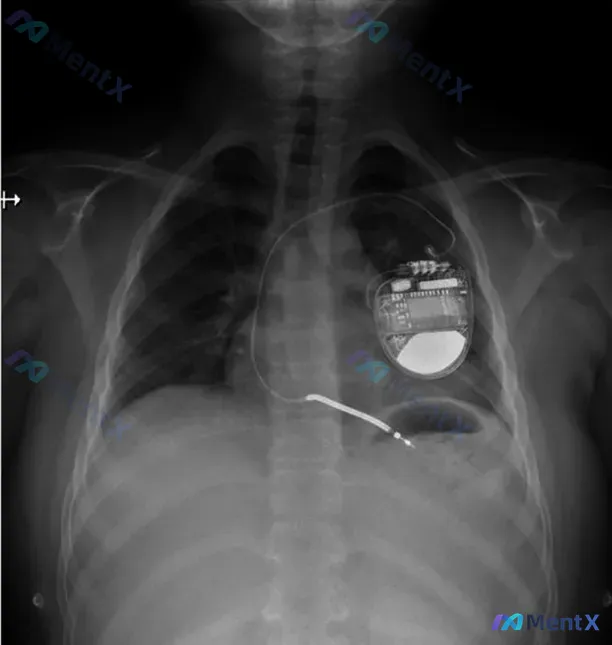

ICD植入术后胸片惊呆:导线怎么跑到胃泡上面去了?

患者是糖原贮积病(GS)患者,植入了经静脉植入式心律转复除颤器(ICD)。

关键影像表现(胸部正位片)

按ABCDE扫了一遍:

- 气道/肺/胸膜:气管居中,肺野清晰,肺门不大,肋膈角锐利,没什么问题。

- 心影/大血管:形态大小大致正常。

- 其他(关键):左侧胸壁确实有ICD发生器,但导线走向完全不对——正常应该经锁骨下静脉到上腔静脉,进右房/右室。但这根导线直接向下穿了纵隔,过了横膈,尖端停在左上腹胃泡上方/膈下区域。

📋答案:ICD导线异位/穿孔(进入腹腔)